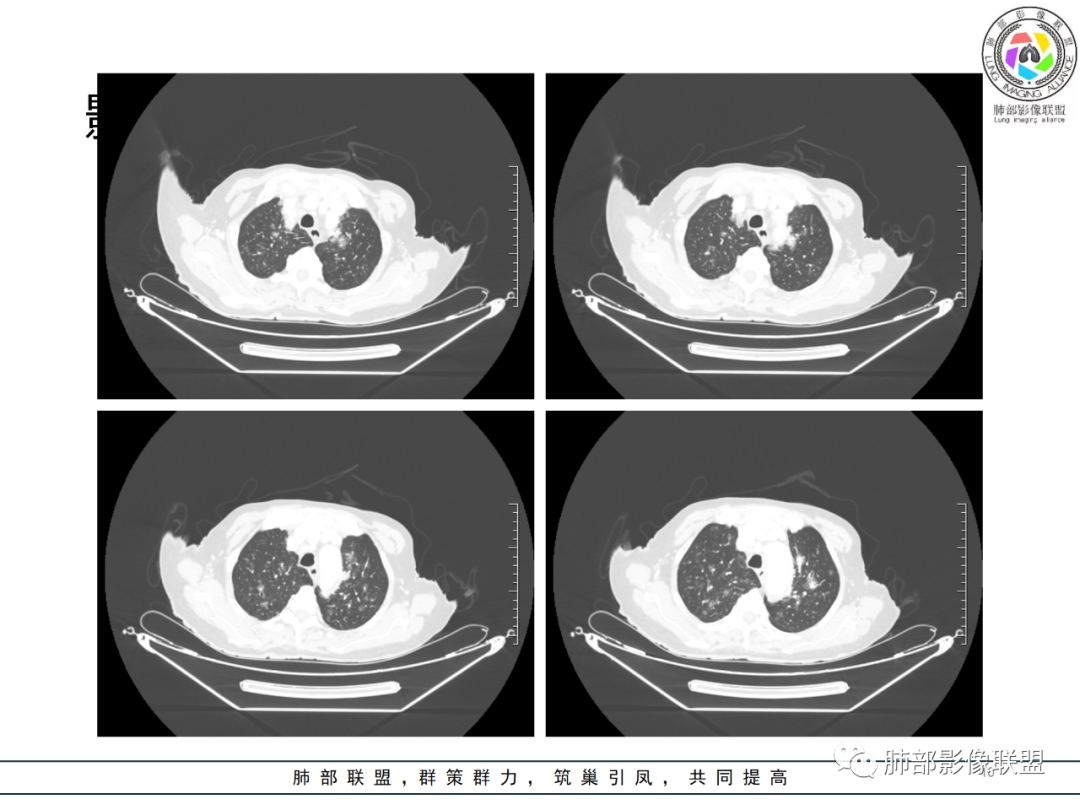

影像资料

老年女性,发热起病,两肺散在斑片状影,三个月后两肺病灶进展,支气管血管束增厚,结合发热病史、实验室检查LCH增高,肾脏及腹膜后淋巴结肿大,结合以上综合考虑符合淋巴瘤表现。

老年女性 3个月前发热,双肺支气管血管束增粗改变。3个月后再次发热,影像见双肺广泛支气管血管束明显增粗,较前进展,并延续进入纵隔,另外增强见双肾周增多软组织密度,左肾明显且肾门处形成肿块样改变。综合考虑肿瘤性病变可能性大,1.小圆细胞肿瘤类病变,淋巴瘤?2 全身组织细胞类病变,如ECD,需要看看骨组织有无问题。3 左肾恶性肿瘤并淋巴道播散,如弥漫性尿路上皮癌。最后考虑 淋巴瘤>ECD>左肾恶性肿瘤并转移。

老年女性,发热,白细胞不高,CRP增高,LDH增高,糖尿病。两肺支气管血管束周围实变、GGO,支气管相对通畅,提示淋巴间质或血管来源。三个月明显进展伴双肾浸润性病变、腹膜后淋巴结肿大,轻-中等程度强化。考虑淋巴瘤,鉴别系统性疾病(IgD4、血管炎)。

老年女性,双肺支气管管壁增厚,沿血管束走形分布结节及斑片影,复查病灶增多增大,部分呈点晕征改变,腹部左肾盂软组织密度影,周边淋巴结增大。考虑肿瘤并肺内转移,淋巴瘤?鉴别真菌感染,曲霉菌?

女性,82岁,发热5天入院,双肺自肺门处血管束增粗,扭曲,三个月后多发结节及实变影,延支气管血管束分布,部分支气管近端堵塞,左肾异常占位?伴有双侧肾上腺增粗,实验室血象略高,考虑IgG4?结节病?淋巴瘤?进一步穿刺活检。

82岁女性,反复发热入院,查外周血白细胞升高,抗生素治疗可缓解,支持细菌感染性发热,结合肾脏肿瘤,考虑泌尿系感染发热;CT提示双肺多发毛玻璃影,右下肺多发大结节影,3月复查,双上肺毛玻璃影/混合毛玻璃影增多,部分呈点晕征,右下肺多发肿块,可见支气管穿行,双下肺中轴间质增厚,左肾占位,肺部病变考虑:1.淋巴瘤 2.肾癌肺转移

老年女性,近期反复的发热,胸部CT基础尚可,心影增大,双肺下叶血管束增粗,3个月后复查 提示双肺多发磨玻璃密度影,并有磨玻璃影内部血管的穿行,双肺下叶血管束的增粗,纵隔窗下未见纵隔肿大的淋巴结,血管通畅,未见血管壁的增厚,左肾肿瘤?肺内病变不符合支气管束分布,暂不考虑吸入性,考虑淋巴管或血管源性病变。总体考虑非感染性病变可能性大,血管炎?淋巴瘤?